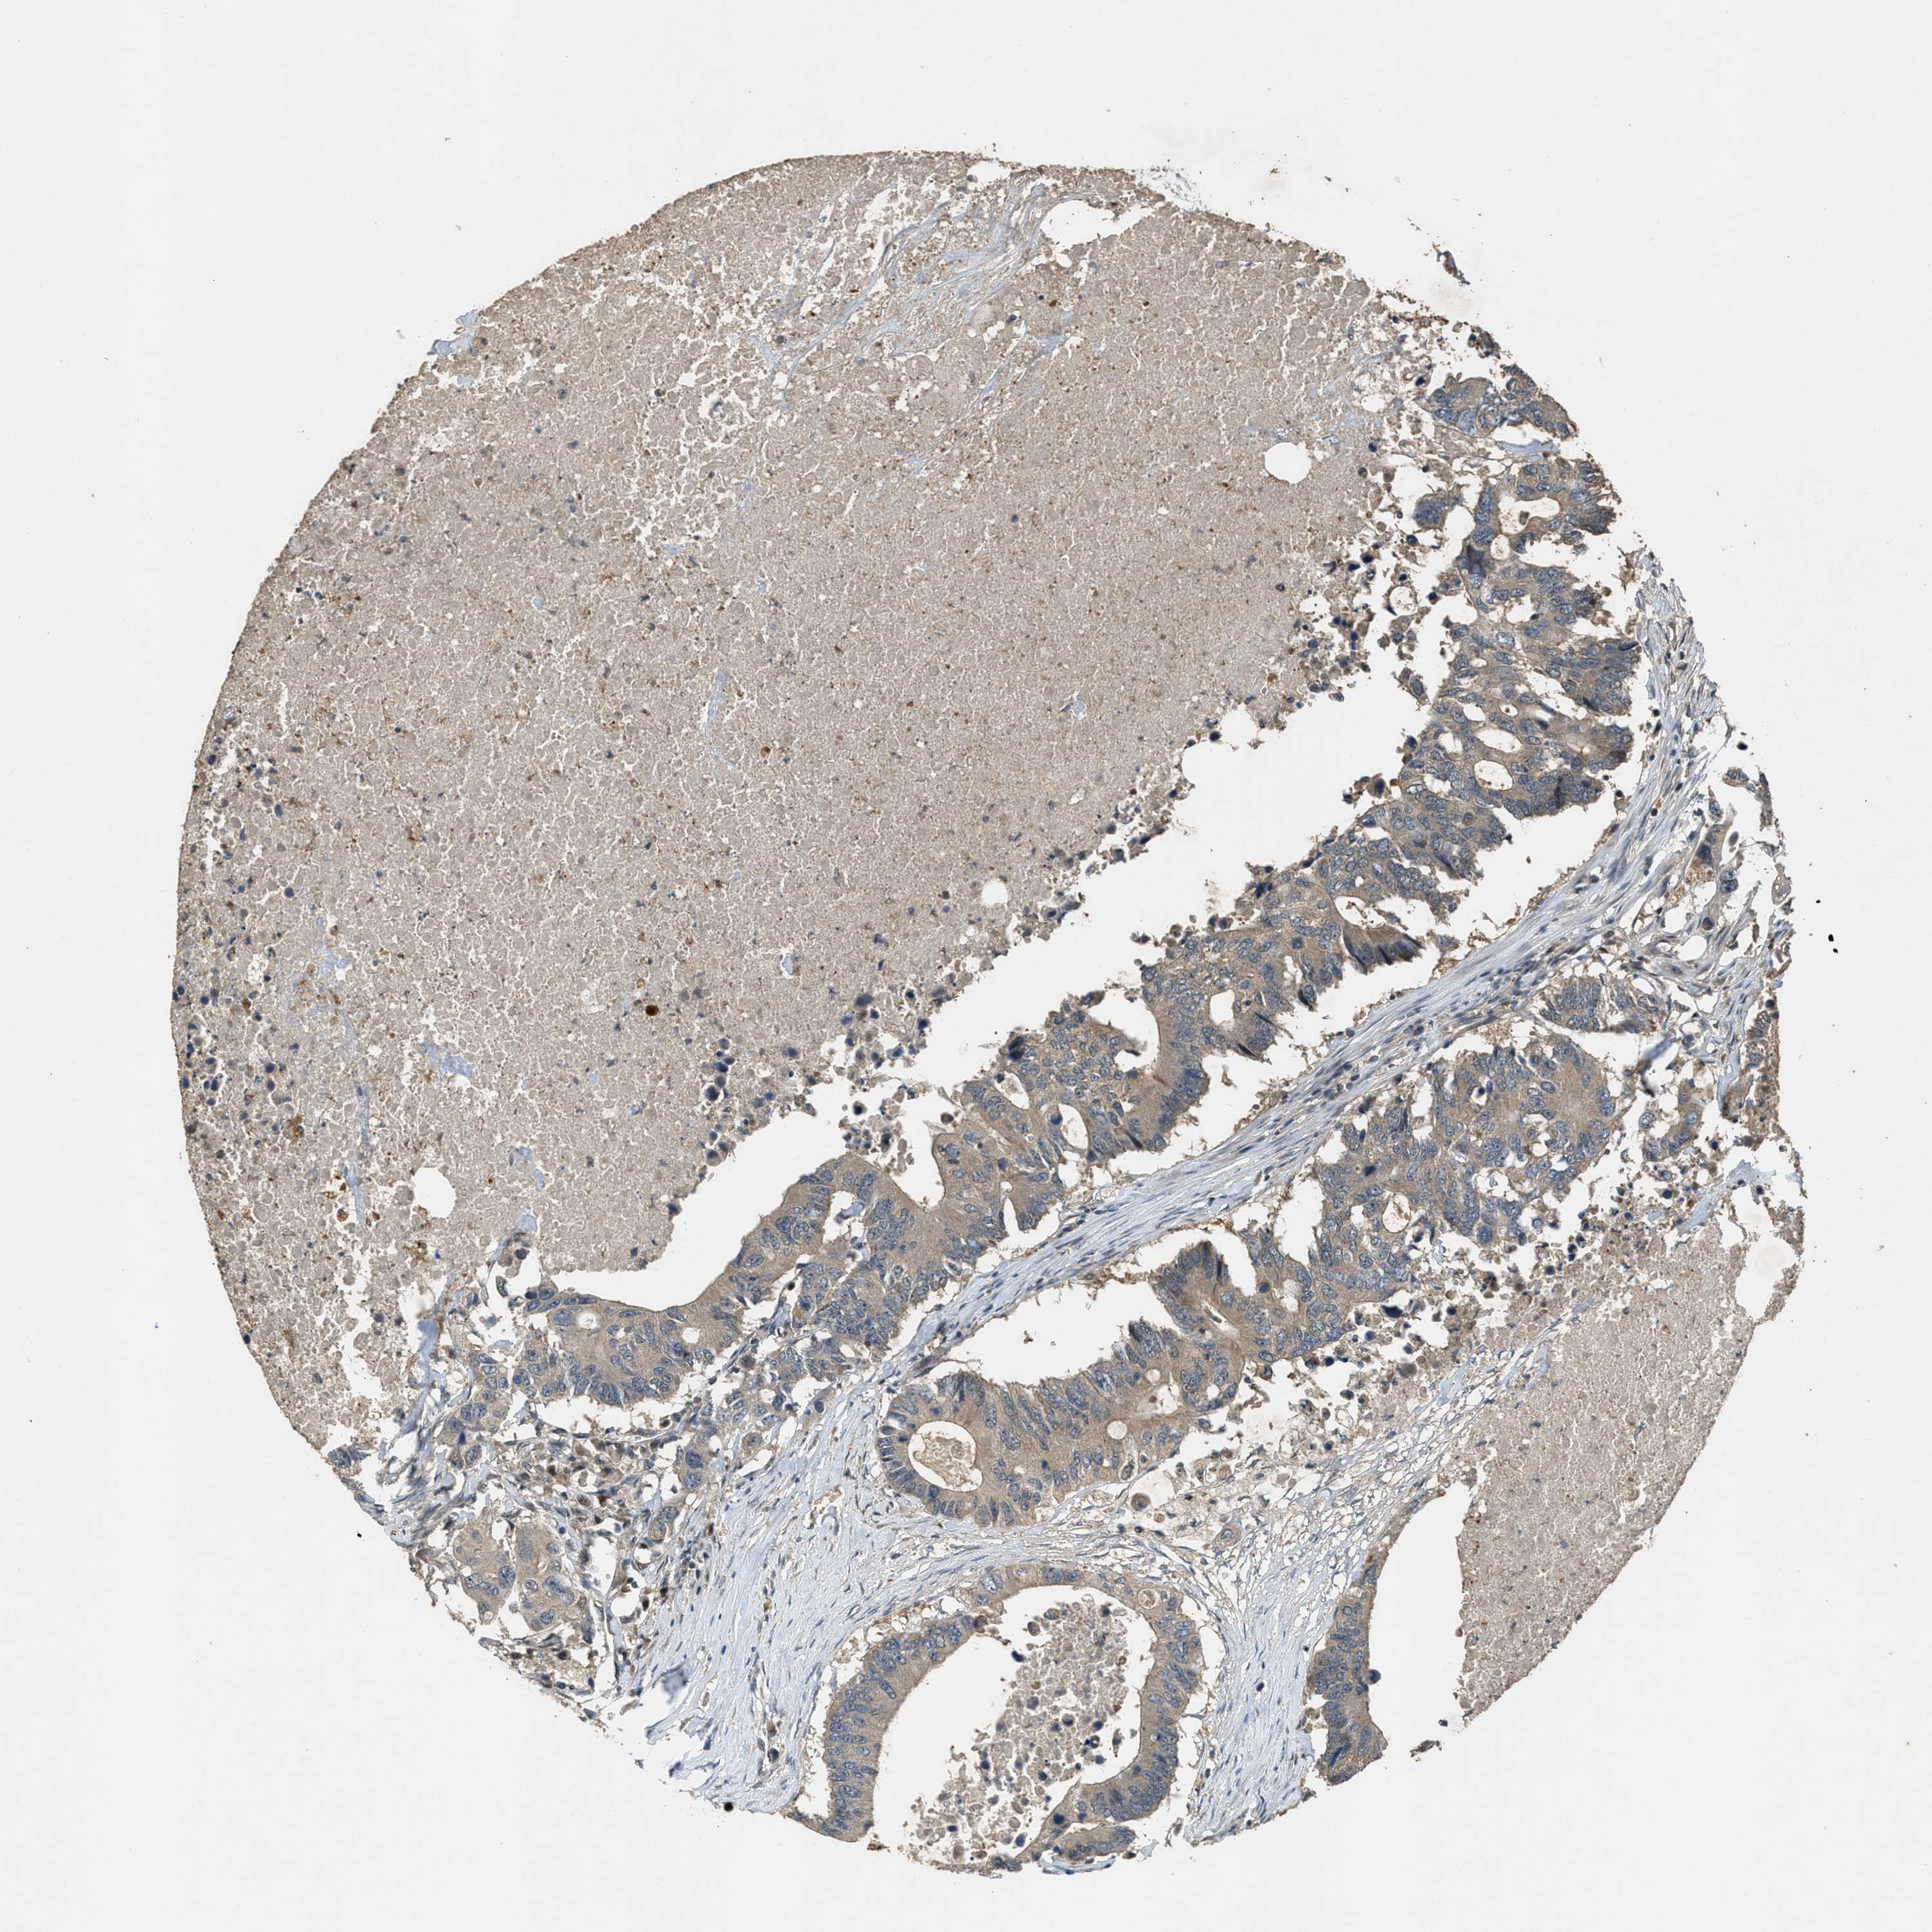

CANCER COLORECTAL CANCER Show tissue menu

Colorectal cancer

Human cancer

Rectum adenocarcinoma